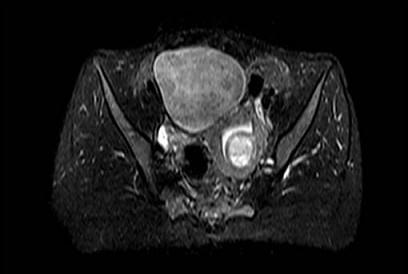

问题 35岁女性患者,曾行剖宫产手术,有痛经史5年,近来加重,行MRI检查,如图所示,请选择正确的答案 ( )

选项 A、卵巢表皮样囊肿 B、卵巢粘液性囊肿 C、子宫颈癌 D、卵巢囊肿 E、子宫内膜异位症

答案 E